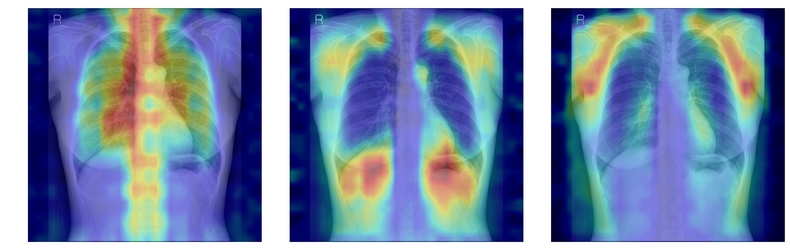

연구팀은 여기에 더해 AI가 실제로 어떤 뼈를 근거로 삼아 판단하는지까지 확인할 수 있도록 ‘설명 가능성’ 평가 체계를 설계했다. 뼈를 모두 가린 상태에서 특정 뼈 부위를 추가해 성능이 얼마나 향상하는지 확인하는 ‘차단 분석 방식(Δbone)’과 Grad-CAM으로 나타난 AI의 주목 영역이 실제 뼈 위치와 얼마나 일치하는지를 계산하는 ‘유의성 지도 방식(IoUbone)’을 통해, AI가 임상적으로 중요한 뼈 구조를 근거로 판단하는지를 정량적으로 검증했다.

그 결과, DINOv2 모델에 LoRA 방식을 적용한 모델이 AUC 0.93(95% CI 0.92–0.94)로 가장 높은 예측 성능을 보였다. 이 모델은 뼈 구조 활용도가 가장 높고, 주목 영역의 타당성에서도 우수해, 예측력과 설명 가능성이 균형 있게 확보된 최적 모델로 평가됐다.